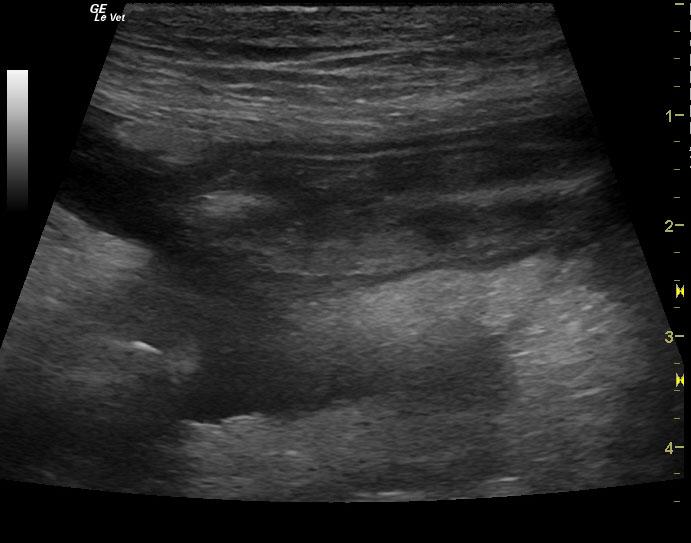

A 6-year-old female spayed Hound mix dog was presented for decreased appetite, increased drinking, and watery diarrhea for 4 days. Physical exam found soft, fluid filled bowels on abdominal palpation. An anti-diarrheal injection was administered, and the patient was discharged with oral anti-diarrheal medication, along with Tylan powder. Approximately 1 week later, the patient presented for persistent decreased appetite, lethargy, and watery stool. Physical exam found patient bright and alert, with pink mucous membranes, normal CRT, heart and lungs clear, a slightly distended abdomen, and no palpable masses found. Blood chemistry revealed hypoproteinemia, hypoalbuminemia, hypocalcemia, and hypocholesterolemia. CBC found high platelet count. Fecal was negative.